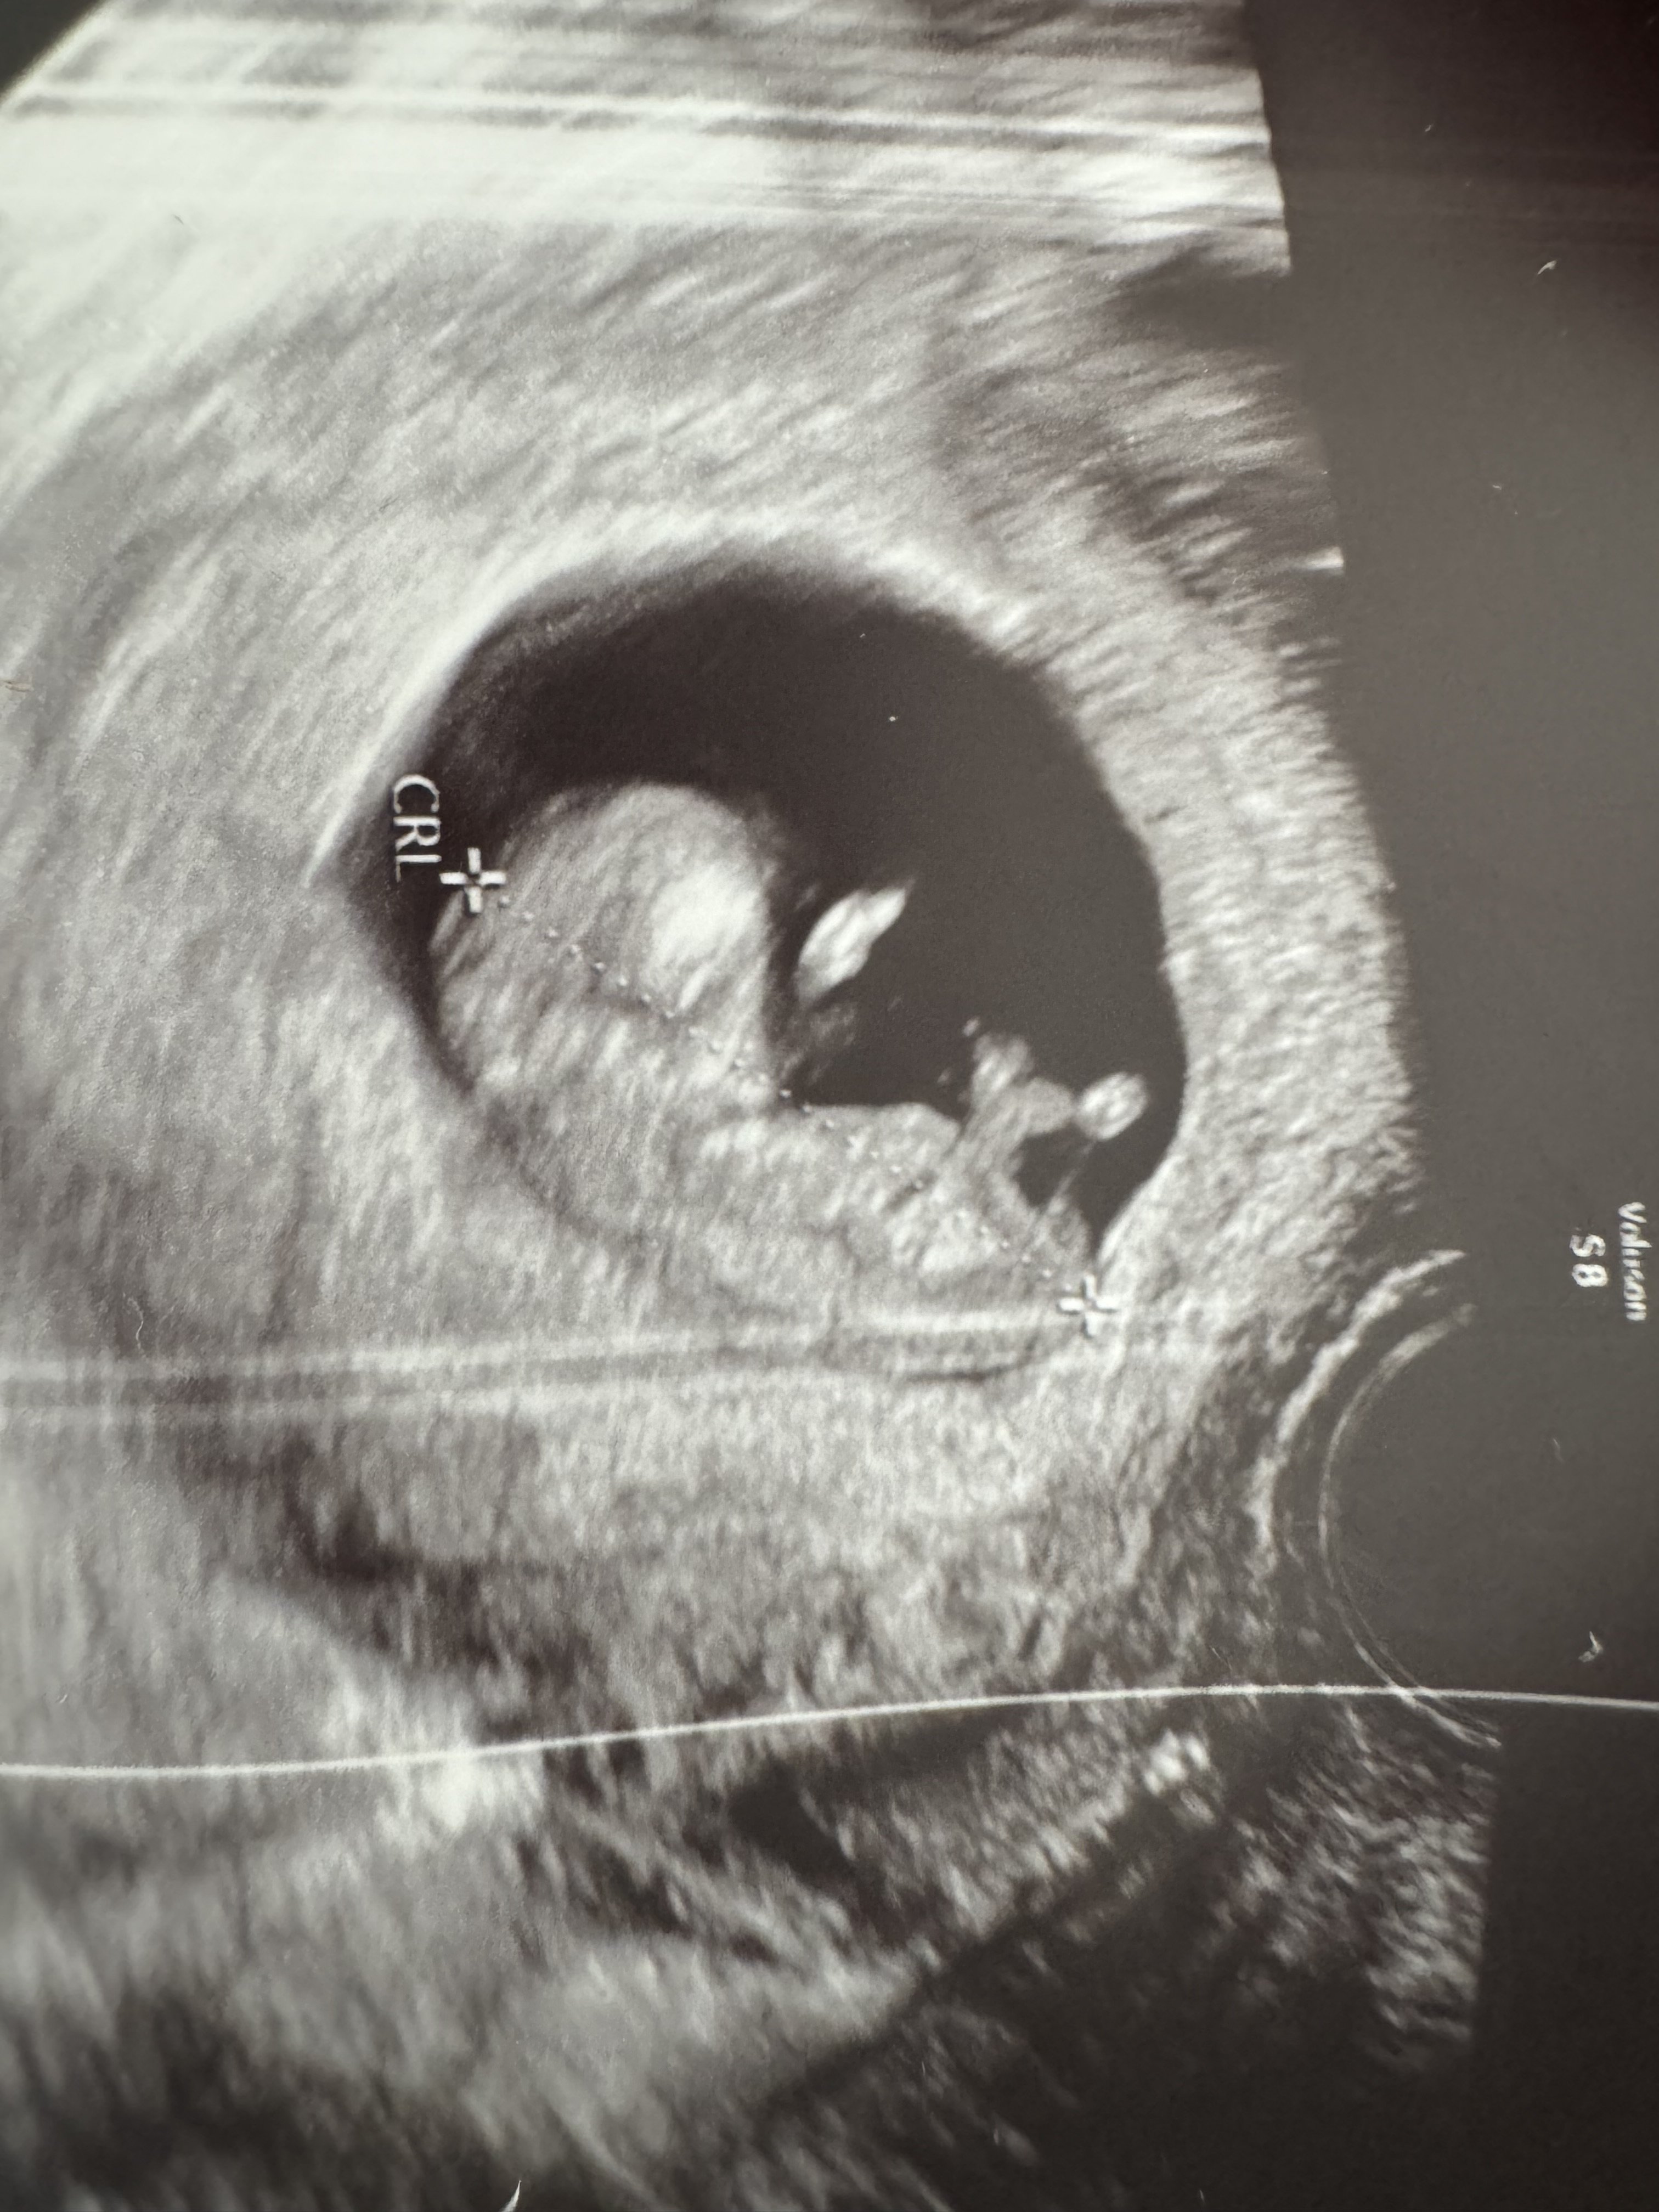

Jestem w 11 tyg zaraz wchodzę w 12 tydzień czekam za prenatalnymi we wtorek ogólnie od początku ciąży słyszę jakieś problemy normy i sam stres . Lekarka moja stwierdziła że nie ma wód płodnych dziecko się dusi i ma nadzieję że dotrwam do prenatalnych bo sama jest ciekawa co tam wyjdzie . 3 h później pojechałam za namową lekarza innego po konsultacji telefonicznej na izbę przyjęć we Wrocławiu gdzie Pani doktor dokładnie mnie zbadała i powiedziała że wody są dziecko ma miejsce żeby się ruszać co nawet zaobserwowałyśmy na ekranie że się rozpycha faktycznie stwierdziła że wód mogło by być więcej ale mówiła też że na tak wczesnym etapie jest wszystko malutkie że te wody jeszcze mogą nająć bo one będą nachodzić całą ciążę i raz może być ich więcej raz mniej bo dzidzia też rośnie . Kazala spokojnie czekać do prenatalnych i pić 2-3 l wody dziennie . Bardzo się denerwuje bo w sumie to jest nasz mały cud po wielu latach starań i nie udanych ifv nie wiem co myśleć . Dołączam zdj USG z 1 i 2 gabinetu widać różnicę odrazu

Wiesz co na tych zdjęciach jest inny kąt w ogóle i na pierwszym pęcherzyk jest przez to zakrzywiony. Po prenatalnych będziesz wiedziała jak oblicza ile masz dokładnie wód. Na tą chwilę nic więcej nie można powiedzieć. Postaraj się nie myśleć o tym i nie denerwować, bo to może zaszkodzić bardziej. Wtorek już tuż tuż. Trzymaj się!